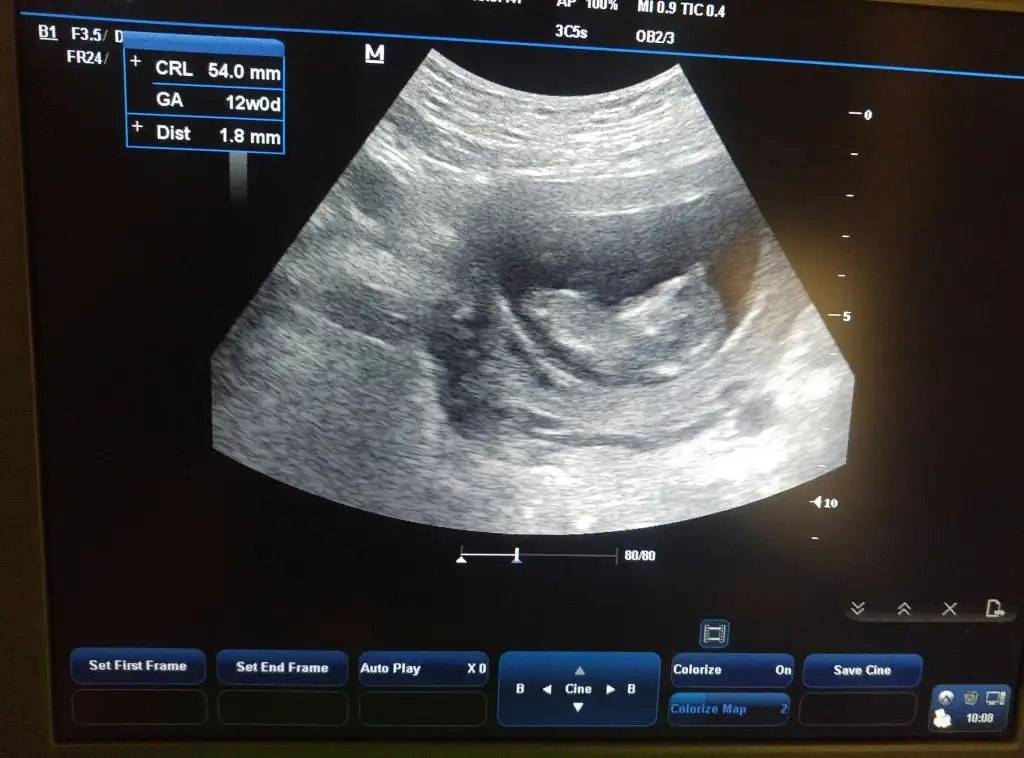

Nubu göremiyorum görüntü olarak kıza benzettim varsa 11 hafta paylaşın netleştirim kızmı erkekmiEki Görüntüle 2307451 Merhabalar vizede yorum yapar mısınız 12 hafta 6 günlük doktora sordum belli değil soldaysa kız sağdaysa erkek diyorlar dedi dalga geçer gibi